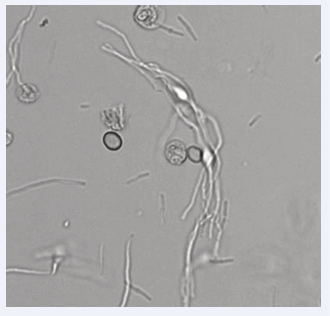

A 91-year-old man presented on June 17, 2024, to the Emergency Department of Pio XI Hospital of Desio, Italy, with fever and hematuria. Laboratory tests revealed a flogistic/septic condition: WBC were 60,5 x 109/L (Reference Interval (RI) 4-11 x 109/L), PCR 246 mg/L (RI< 5 mg/L), PCT 158.80 ng/mL (RI <0,5 ng/mL). A chest x-ray showed a large right basal parenchymal thickening and a bibasilar pleural effusion. The patient was admitted to the Internal Medicine Department and was diagnosed as having pneumonia with mild respiratory failure. He was immediately treated with ceftriaxone disodium and azithromycin dihydrate. Urinalysis was performed during hospitalization and showed the following results: pH = 5.5 (RI 4.5–9.0); relative density = 1.010 (RI 1.005–1.040); hemoglobin (+3) (RI: +/- to + 3); leukocyte esterase = 500 leu/μL (RI < 25 leu/μL); nitrites = negative. Microscopic examination of the urine sediment, with an automated analyzer, revealed the presence of erythrocytes (90/ μL), leukocytes (267/μL), and bacteria (267/μL). These findings suggested the possibility of a UTI. Additionally, we observed some uncommon elements known as spheroplasts. Spheroplasts are bacteria that develop the shape shown in figures 1,2 when exposed to sub-inhibitory levels of ß-lactam antibiotics.

Figure 4: The Spheroplasts can have similar morphology to hyphae leading to  the misclassification as yeasts.